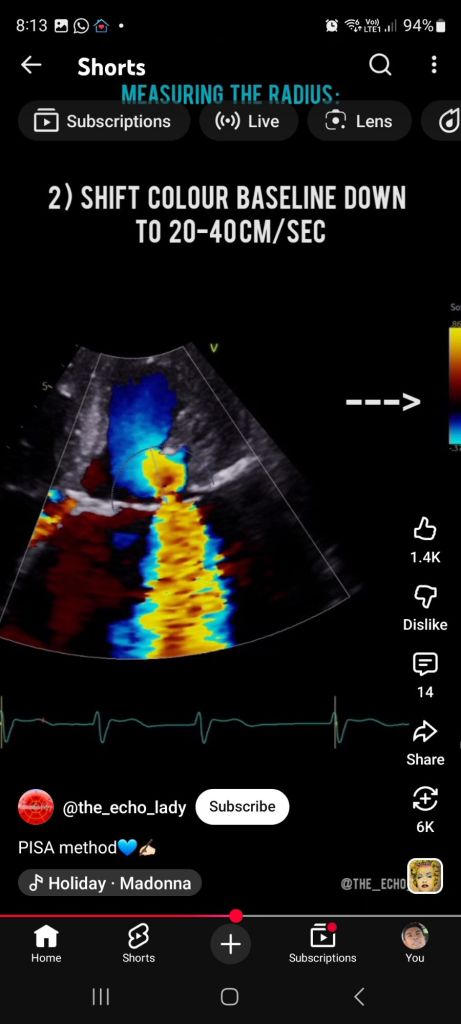

On color Doppler:

Flow suddenly changes color (e.g. red → blue)

That sharp boundary = aliasing velocity line